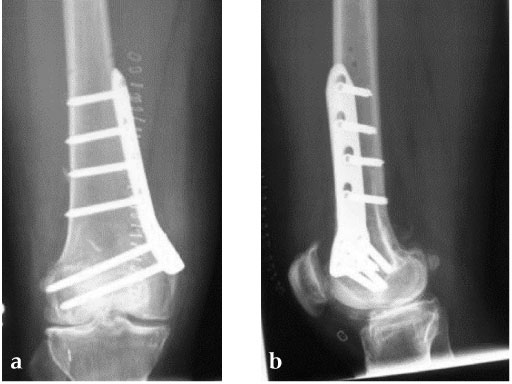

An anteromedial skin incision is used. This skin incision can be reused and expanded during subsequent knee surgery. The vastus medialis muscle is dissected from the septum, the medial patellofemoral ligament (MPFL) and the distal insertion of the vastus medialis muscle are partially incised. Two blunt Hohmann retractors are placed around the distal femur. The oblique osteotomy starts in the medial supracondylar area and ends in the lateral condyle, approximately 10 mm inside the lateral cortex. For guiding the closing wedge osteotomy of the distal femur a specific saw guide will be available soon. Alternatively, it is possible to use K-wires inserted under image intensifier control to mark the bone cuts. The saw cuts are made with retractors protecting the soft tissue and vessels. The wedge is removed and the height and depth of the osteotomy can be measured. At this time it is possible to make modifications concerning the wedge size. Closing the wedge must be done gradually by gentle compression of the lower leg laterally, and stabilizing the knee joint medially near the area of osteotomy. This may take several minutes to enable plastic deformation of the lateral cortex to close the osteotomy gap. Leg alignment is checked radiologically after closing with a rigid alignment bar positioned between hip and ankle center. The bar representing the weight-bearing line should pass the preoperatively defined mechanical axis. The plate is inserted from distal under the vastus medialis muscle. The distal drill holes are oriented in a 20 angle inclination on the frontal plane to avoid a posterior perforation of locking head screws in the distal femur. The distal four bolts are placed. A lag screw is positioned in the dynamic hole directly above the osteotomy for compression of the osteotomy site. The screw should be tightened carefully using the image intensifier. The plate is now fixed to the shaft with bolts monocortically, and the lag screw is replaced by a bolt bicortically. The wound is closed in layers after insertion of a drain. The patient is mobilized on the first day after surgery. Partial weight bearing is recommended for 6 weeks, active movement of the knee is enhanced. Biomechanical testing confirmed superior stability of medial closing wedge techniques as compared to lateral open wedge techniques and favourable axial and torsional loading characteristics of the TomoFix medial distal femur (MDF) plate. The plate is now available, as well as a booklet on the operative technique.

27-year-old male developed severe lateral joint line pain after lateral menicectomy.

Case provided by Philipp Lobenhoffer, Hannover, DE